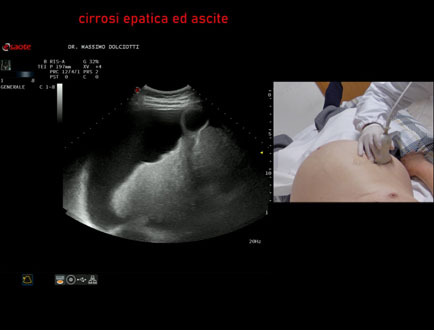

Data inserimento: 16/02/2024

Ecografia del: 14/02/2024

Strumento: Esaote MyLab Eight

Sonda: Convex Multifrequenza 1-8 MHz

Età Paziente: F 87 anni

Motivazione dell'esame: anemia severa, incremento del volume dell'addome.

Commento all'esame: le immagini ed il video documentano il fegato, ridotto di dimensione, ad ecostruttura disomogenea, di aspetto nodulare, a profilo irregolare, con presenza di ascite.

Conclusioni: cirrosi epatica scompensata con ascite (decompensated liver cirrhosis with ascites).